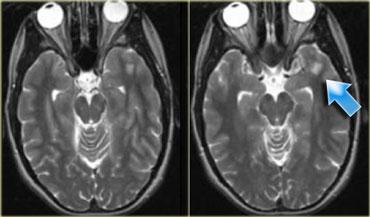

U thần kinh bao (Schwannoma) vùng góc cầu tiểu não với các đặc điểm điển hình của u ngoài trục (Chuỗi xung T2W)

Chuỗi xung T2W cho thấy một u thần kinh bao (schwannoma) nằm ở góc cầu tiểu não (CPA).

Trường hợp này minh họa rõ nét các dấu hiệu điển hình của u ngoài trục.

Có khe dịch não tủy (mũi tên vàng).

Các mạch máu dưới nhện chạy trên bề mặt não bị tổn thương đẩy lệch (mũi tên xanh lam).

Có chất xám nằm giữa tổn thương và chất trắng (mũi tên đỏ cong).

Khoang dưới nhện bị giãn rộng do sự phát triển của tổn thương ngoài trục có xu hướng đẩy lùi não.

Tất cả các dấu hiệu này cho thấy đây là một u ngoài trục điển hình.

Tại vùng góc cầu tiểu não, 90% các u ngoài trục là u thần kinh bao (schwannoma).